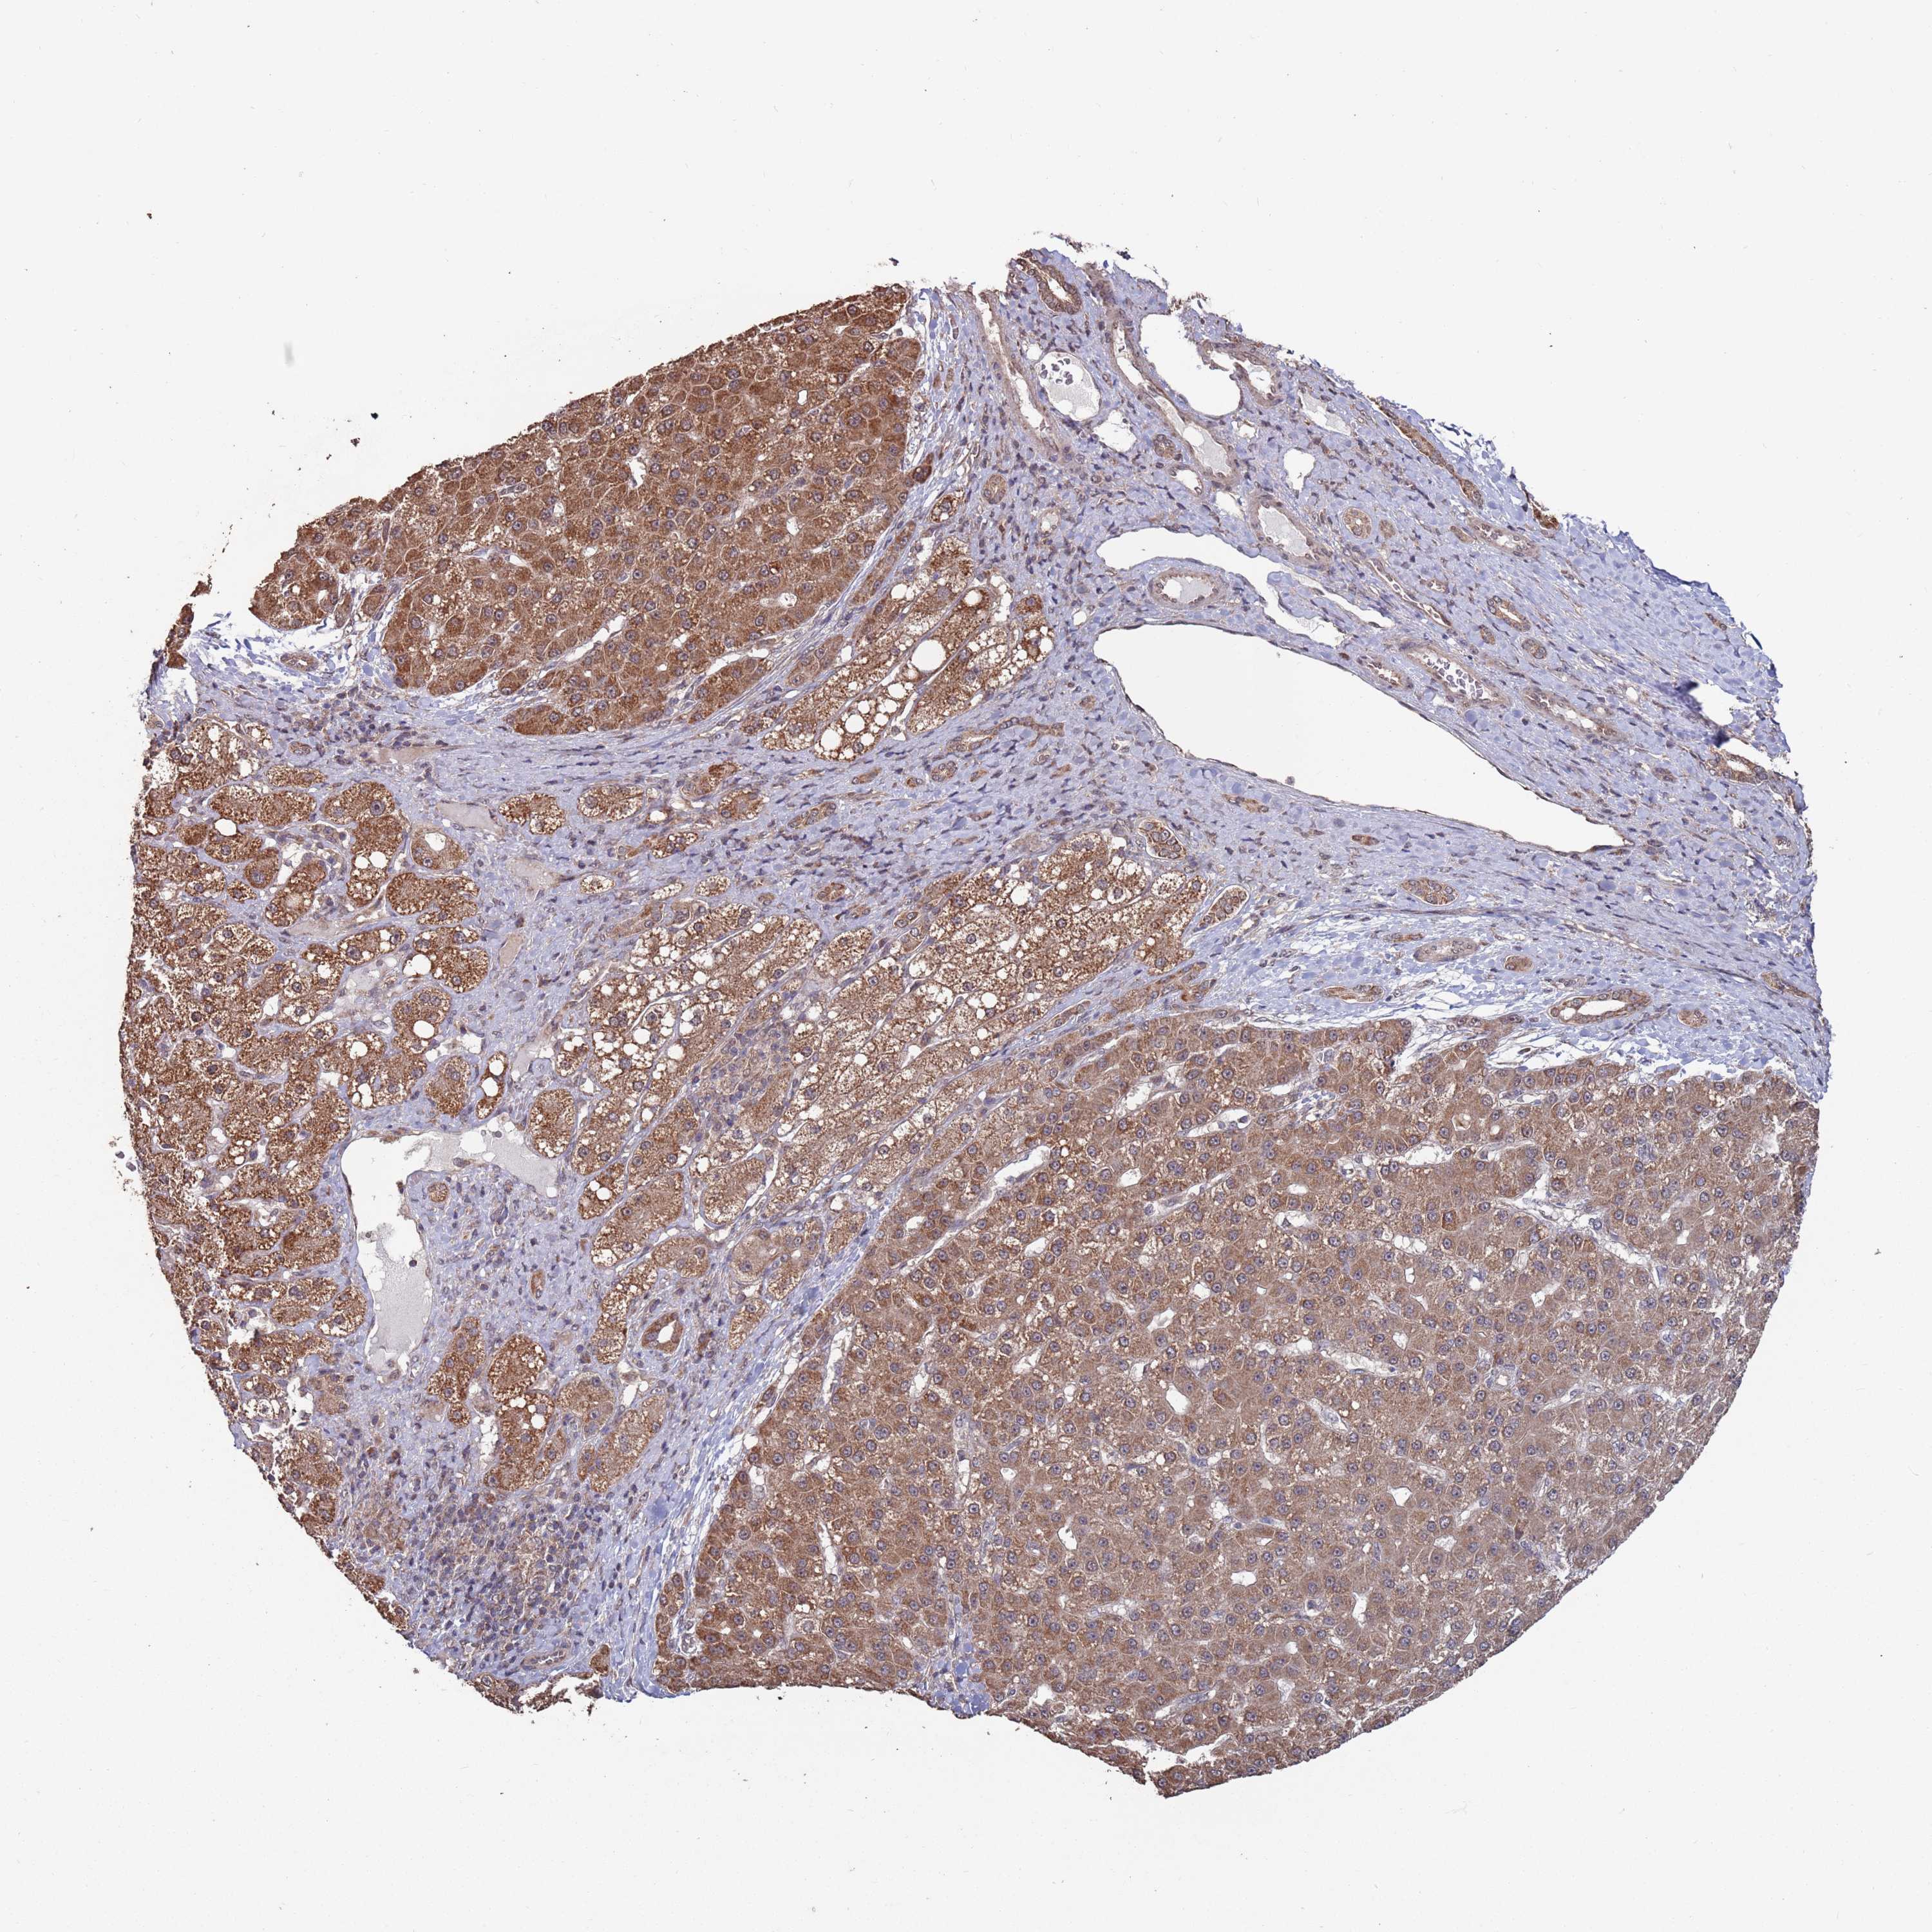

LIVER CANCER - Protein expressioni

A mouse-over function shows sample information and annotation data. Click on an image to view it in a full screen mode. Samples can be filtered based on level of antibody staining by selecting one or several of the following categories: high, medium, low and not detected. The assay and annotation is described here.

Note that samples used for immunohistochemistry by the Human Protein Atlas do not correspond to samples in the TCGA dataset.

Antibody stainingi

Antibody staining in the annotated cell types in the current human tissue is reported as not detected, low, medium, or high, based on conventional immunohistochemistry profiling in selected tissues. This score is based on the combination of the staining intensity and fraction of stained cells.

Each image is clickable and will lead to virtual microscopy that enables deeper exploration of all samples and also displays staining intensity scores, fraction scores and subcellular localization as well as patient and tissue information for each sample.

Antibody HPA046636

Staining

High

Medium

Low

Not detected

Intensity

Strong

Moderate

Weak

Negative

Quantity

>75%

75%-25%

<25%

None

Location

Nuclear

Cytoplasmic/membranous

Cytoplasmic/membranous,nuclear

Cholangiocarcinoma

Carcinoma, Hepatocellular, NOS